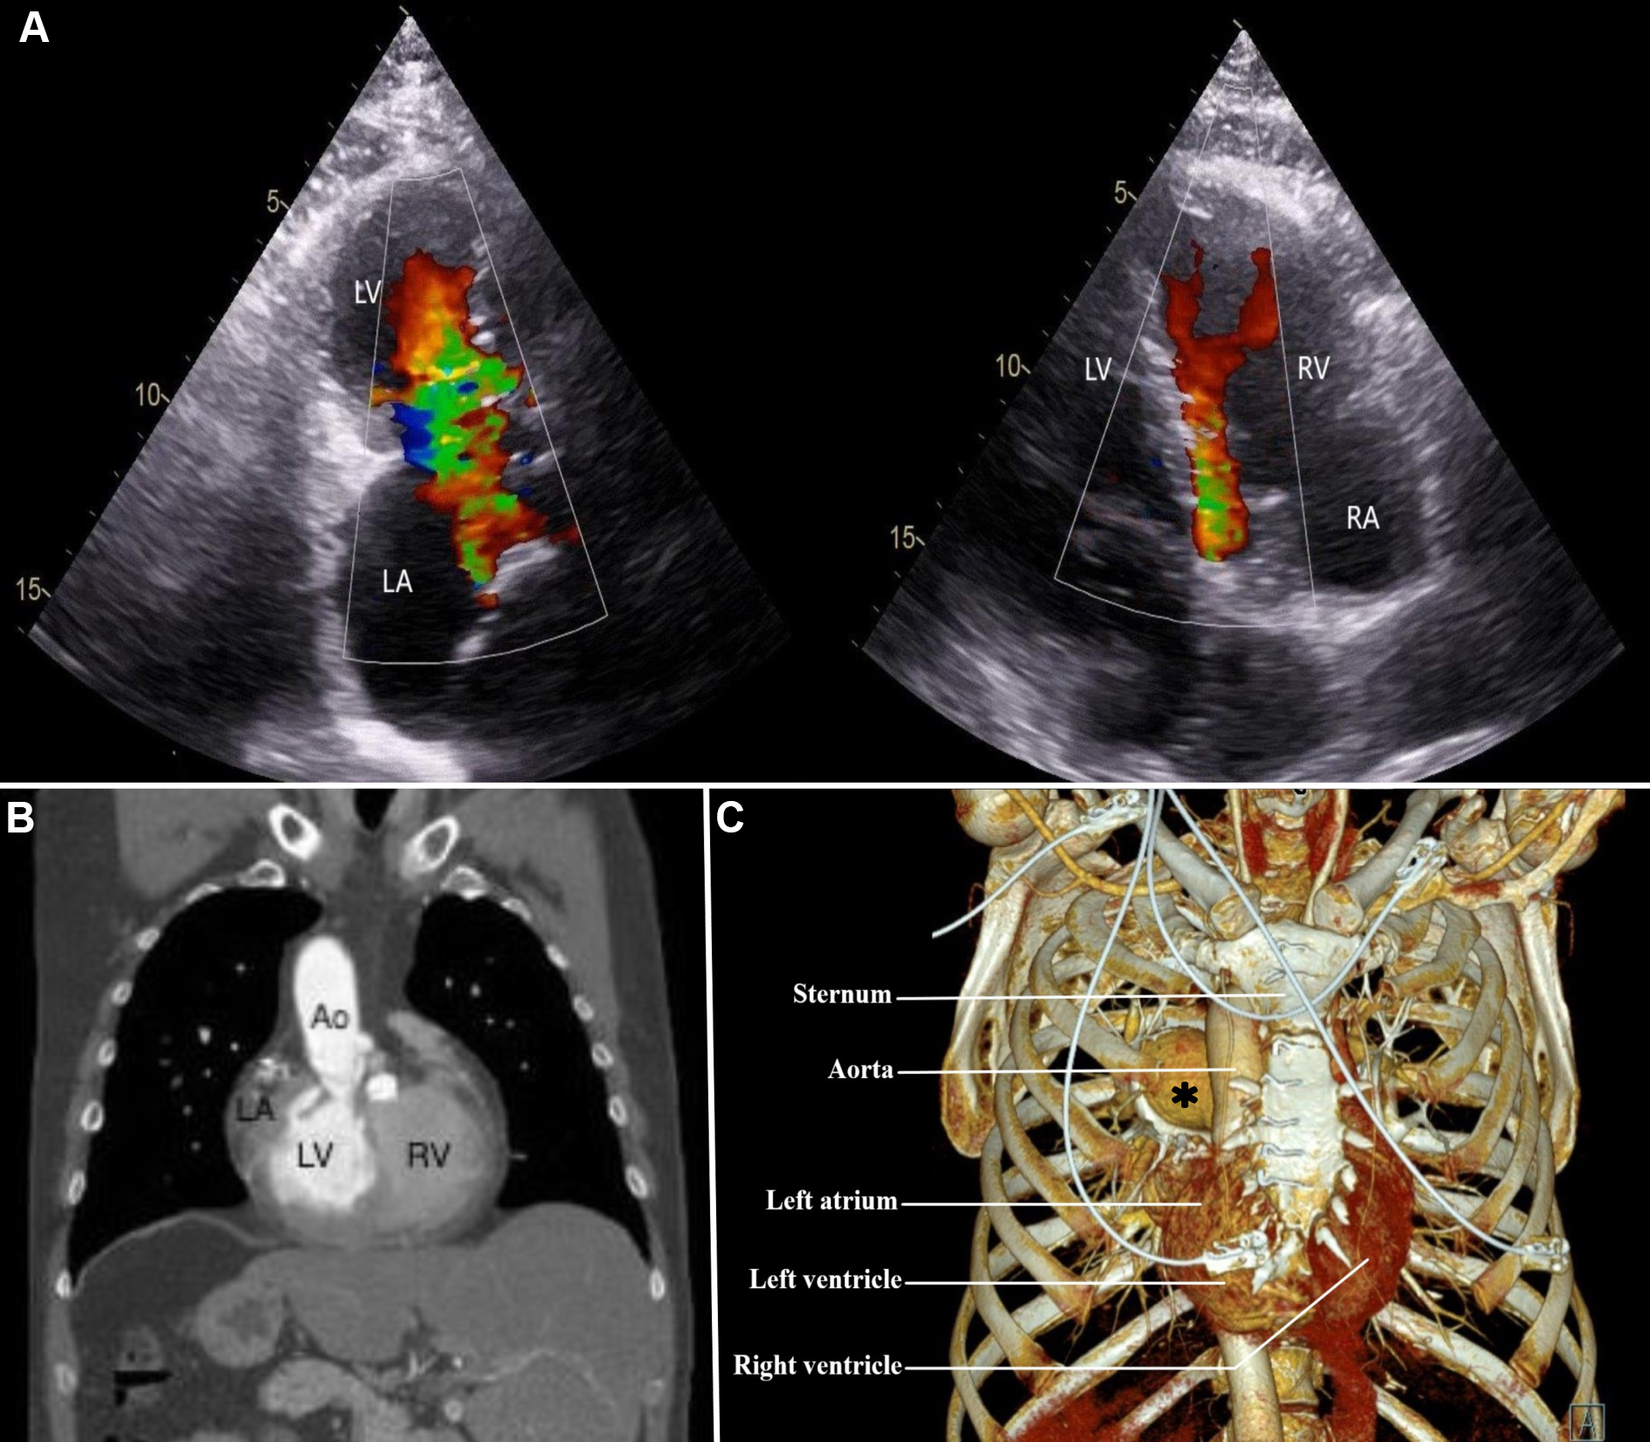

A 50-year-old man diagnosed with dextrocardia and situs inversus totalis (DSIT) was referred at our institution with symptoms of exertional dyspnea due to severe mitral and pulmonary valve regurgitation for surgical replacement of both valves (Figure 1A). A previous surgical closure of an atrial septal defect was performed through conventional sternotomy 30 years ago. Preoperative computed tomography angiography (CTA) of the chest and abdomen as well as a transthoracic echocardiography (TTE) confirmed the DSIT, citing a light rightward rotation of the apex around the central axis, and showed a very complex anatomy of the heart (Figure 1B). The left atrium (LA) and left ventricle (LV) were placed on the right side, the right atrium (RA) and the right ventricle (RV) on the left side, with the apex lying behind the sternum (Figure 1C). CTA also showed the aorta situated anterior and to right of the main pulmonary artery, with the anatomical right pulmonary artery passing under the aortic arch, suggestive of an anatomically corrected malposition of the great arteries with the I-L-D type (1).

Figure 1

(A) preoperative transesophageal echocardiography showing mitral and pulmonary valve regurgitation; (B) computed tomography angiography of the chest and upper abdomen, demonstrating a rightward orientation of the left atrium, and liver at the left side; (C) computed tomography angiography with 3D reconstruction of the chest, illustrating a right-sided location of the left atrium and ventricle from the sternum. Ao, aorta; LA, left atrium; LV, left ventricle; RA, right atrium; RV, right ventricle. Asterisk, right pulmonary artery.